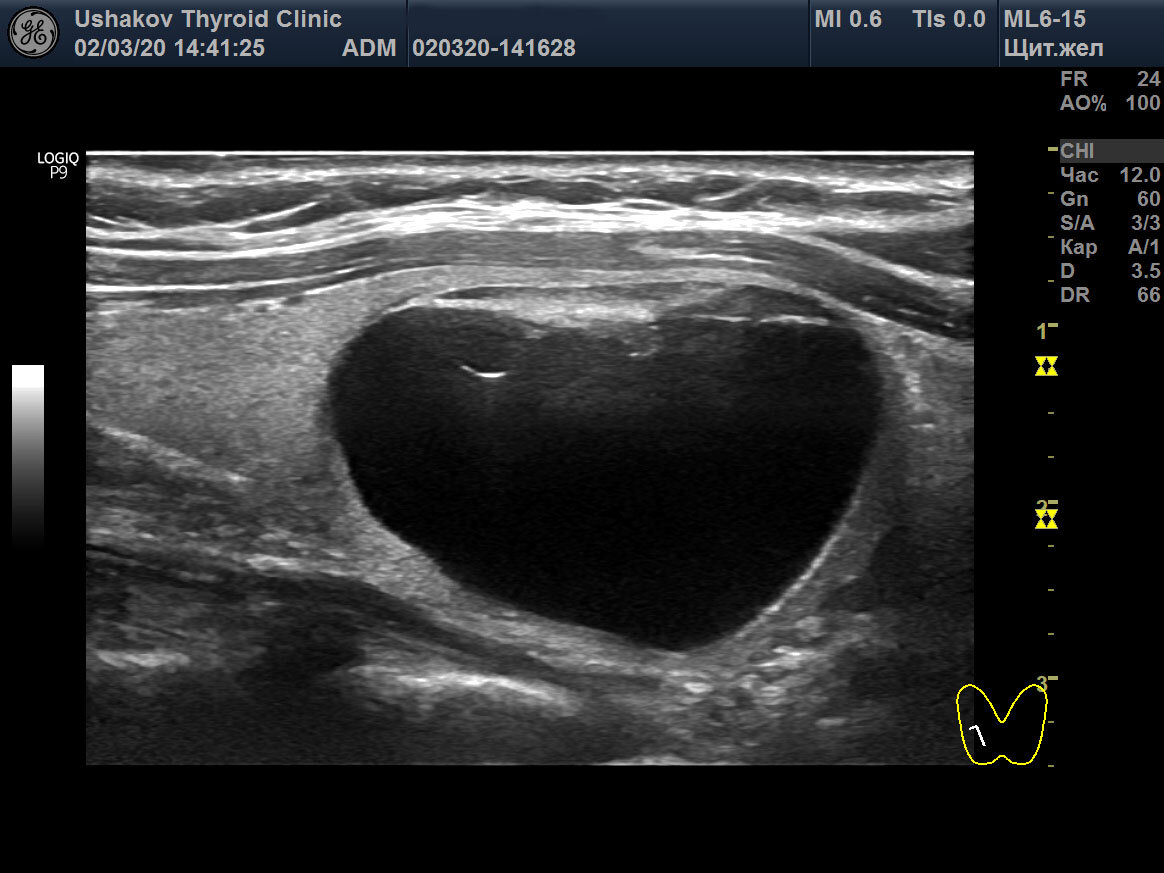

Если в узле значительно преобладает жидкость, то узел доброкачественный. Такой узел называют кистозным или кистой. Никакой рак в жидкости не возникает.

Пункционная биопсия узла щитовидной железы не показана, если ткань составляет менее 50% объема узла, сам узел менее 15-20 мм и остаточная ткань узла не имеет других признаков рака.

Кистозный узел (киста) щитовидной железы. Рисунок из атласа-руководства А.В. Ушакова "Ультразвуковая диагностика рака щитовидной железы по ACR TI-RADS", 2020